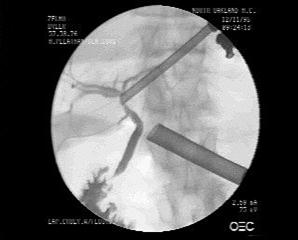

Рисунок 12 – Интраоперационная холангиография (выделение пузырного протока при лапароскопической холецистэктомии, вскрытие его просвета,

канюляция и введение контраста).